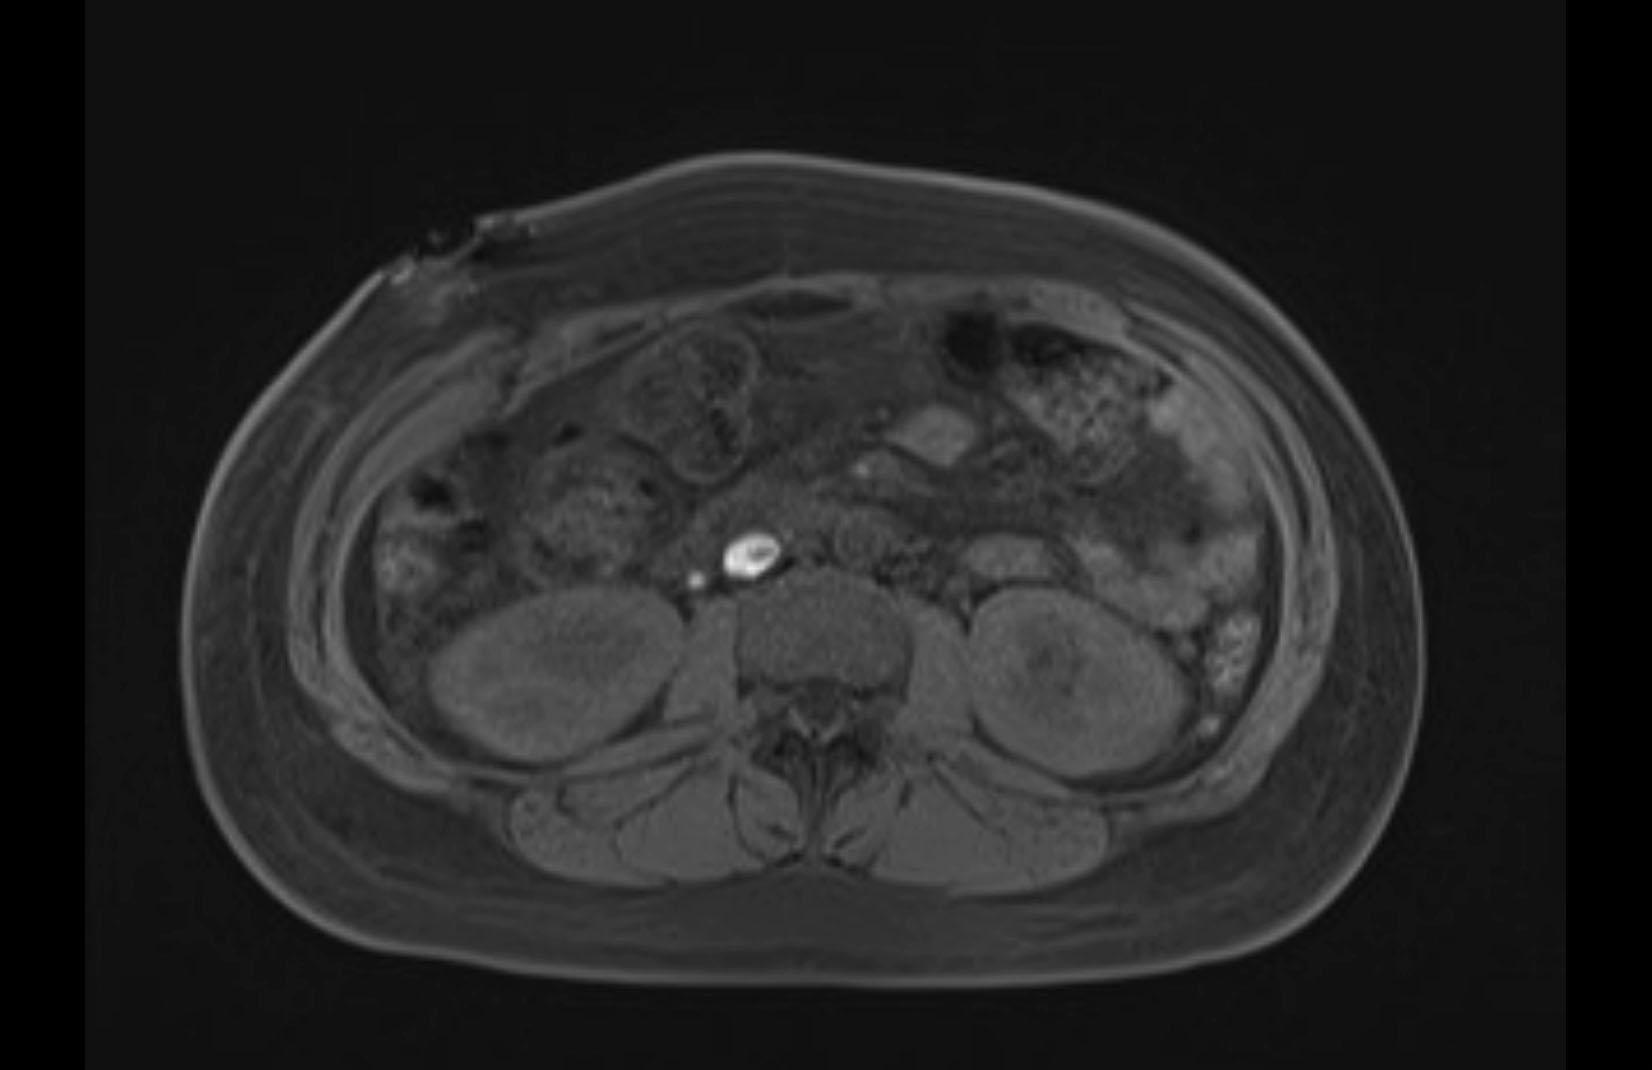

Imaging Analysis

Look through the patient's CT scan to identify any areas of concern for the necessary procedure.

MRI T1

MRI T2

Based on initial findings, which issue(s) would you be most concerned about?